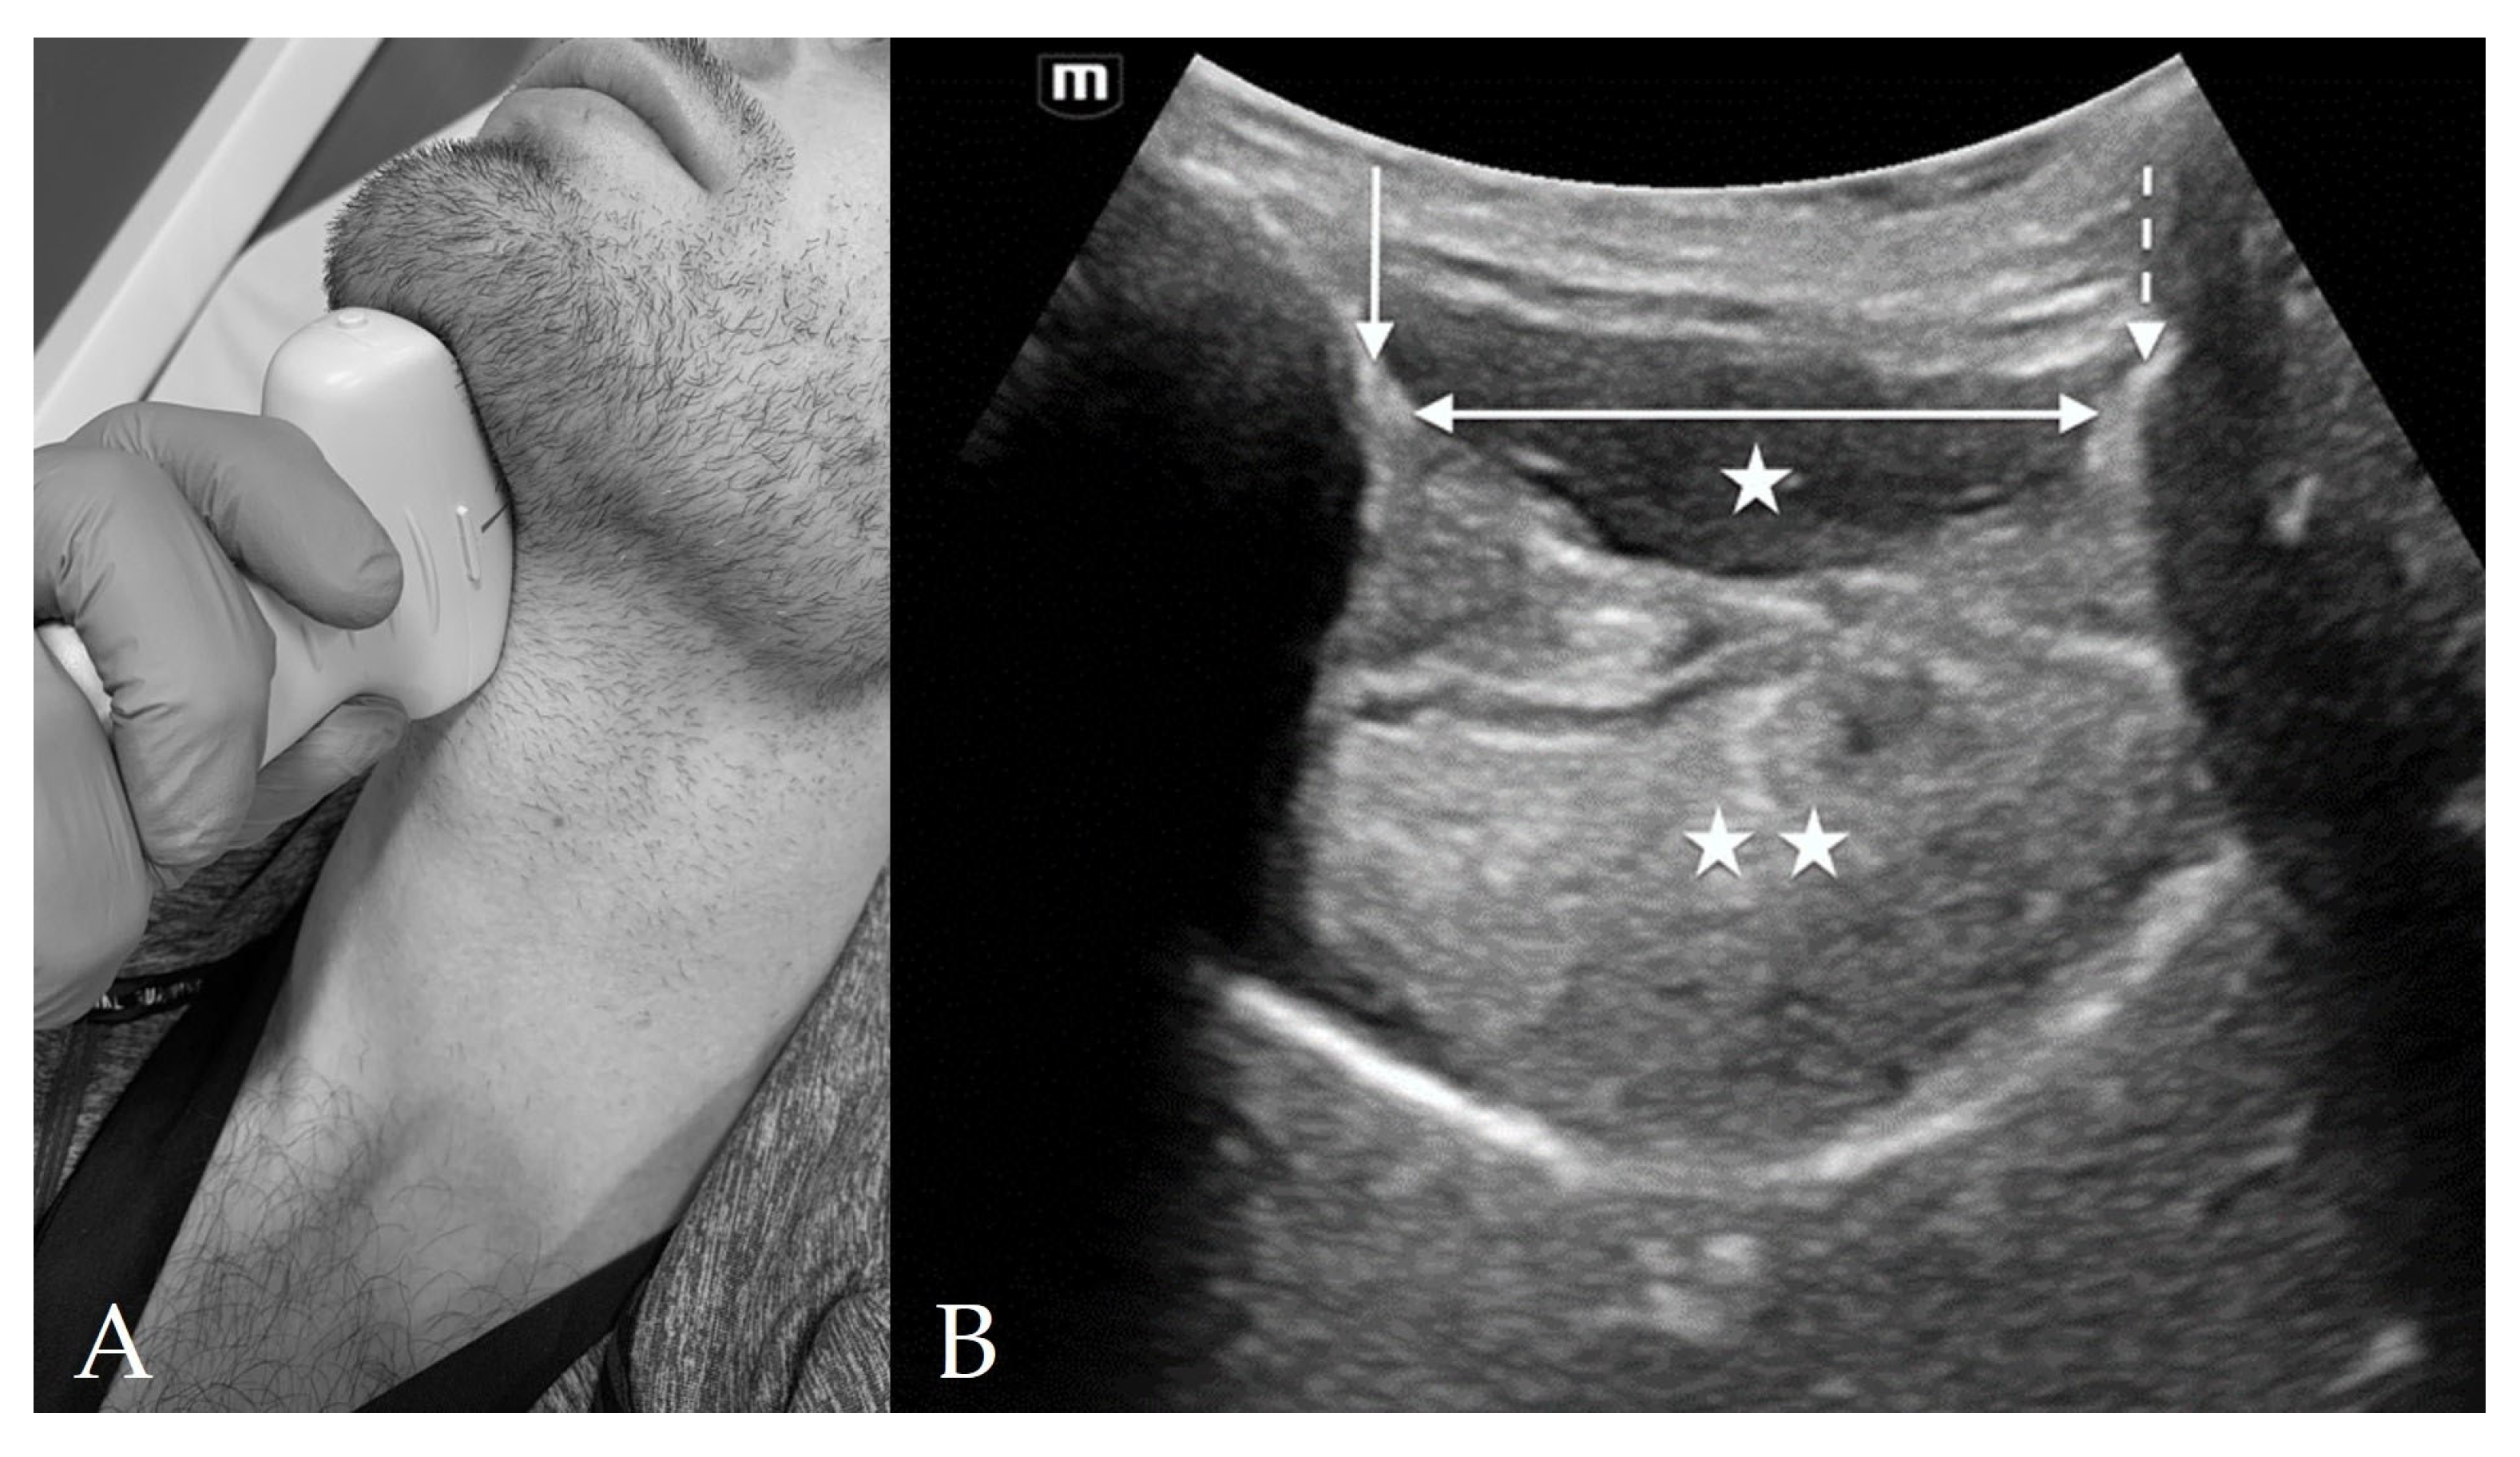

3. Probe Selection and Technique

4.3. Thyroid View